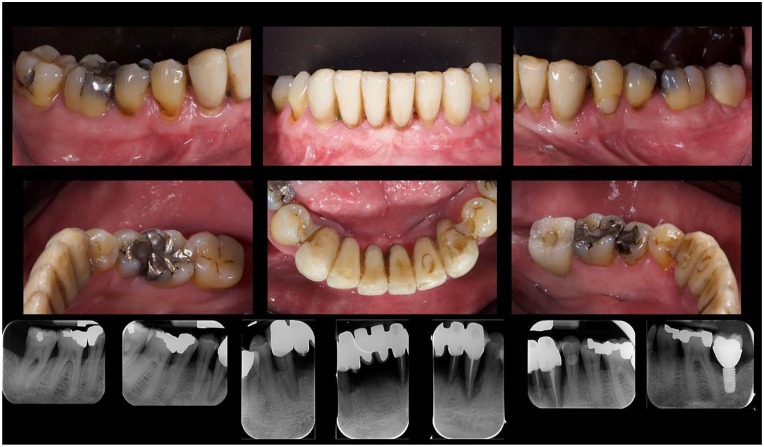

年龄相关性黄斑变性(AMD)是50岁及以上人群视力受损的主要原因,主要影响中央视力。本研究旨在调查牙周病与年龄相关性黄斑病变之间的潜在关联。66岁男性受试者,患有年龄相关性退行性黄斑病变和严重牙周病,评估和治疗。在最初阶段的非手术牙周治疗后,重新评估牙周指标。此外,还进行了用种植体代替无希望牙的拔牙。视网膜地形图用于评估可能的病理消退,并给予适当的抗vegf治疗。结果显示牙周病的消退和退行性黄斑病变的改善。这些初步结果即使令人鼓舞,也应该得到更大规模前瞻性试验的支持。

Age-related macular degeneration (AMD) is a leading cause of significant vision impairment in individuals aged 50 and older, primarily impacting central vision. This study seeks to investigate potential associations between periodontal disease and age-related maculopathy in the analyzed clinical case. A male subject of 66 years old, with age-related degenerative maculopathy and severe periodontal disease, was evaluated and treated. After an initial phase of non-surgical causal periodontal therapy, the periodontal indices were re-evaluated. In addition, the extraction of hopeless teeth replaced by dental implants was performed. A retinal topography was used to assess possible regression of the pathology, and proper anti-VEGF therapy was administered. The results showed a regression of periodontal disease and an improvement of the degenerative maculopathy. These preliminary results, even if encouraging, should be supported by larger prospective trials.